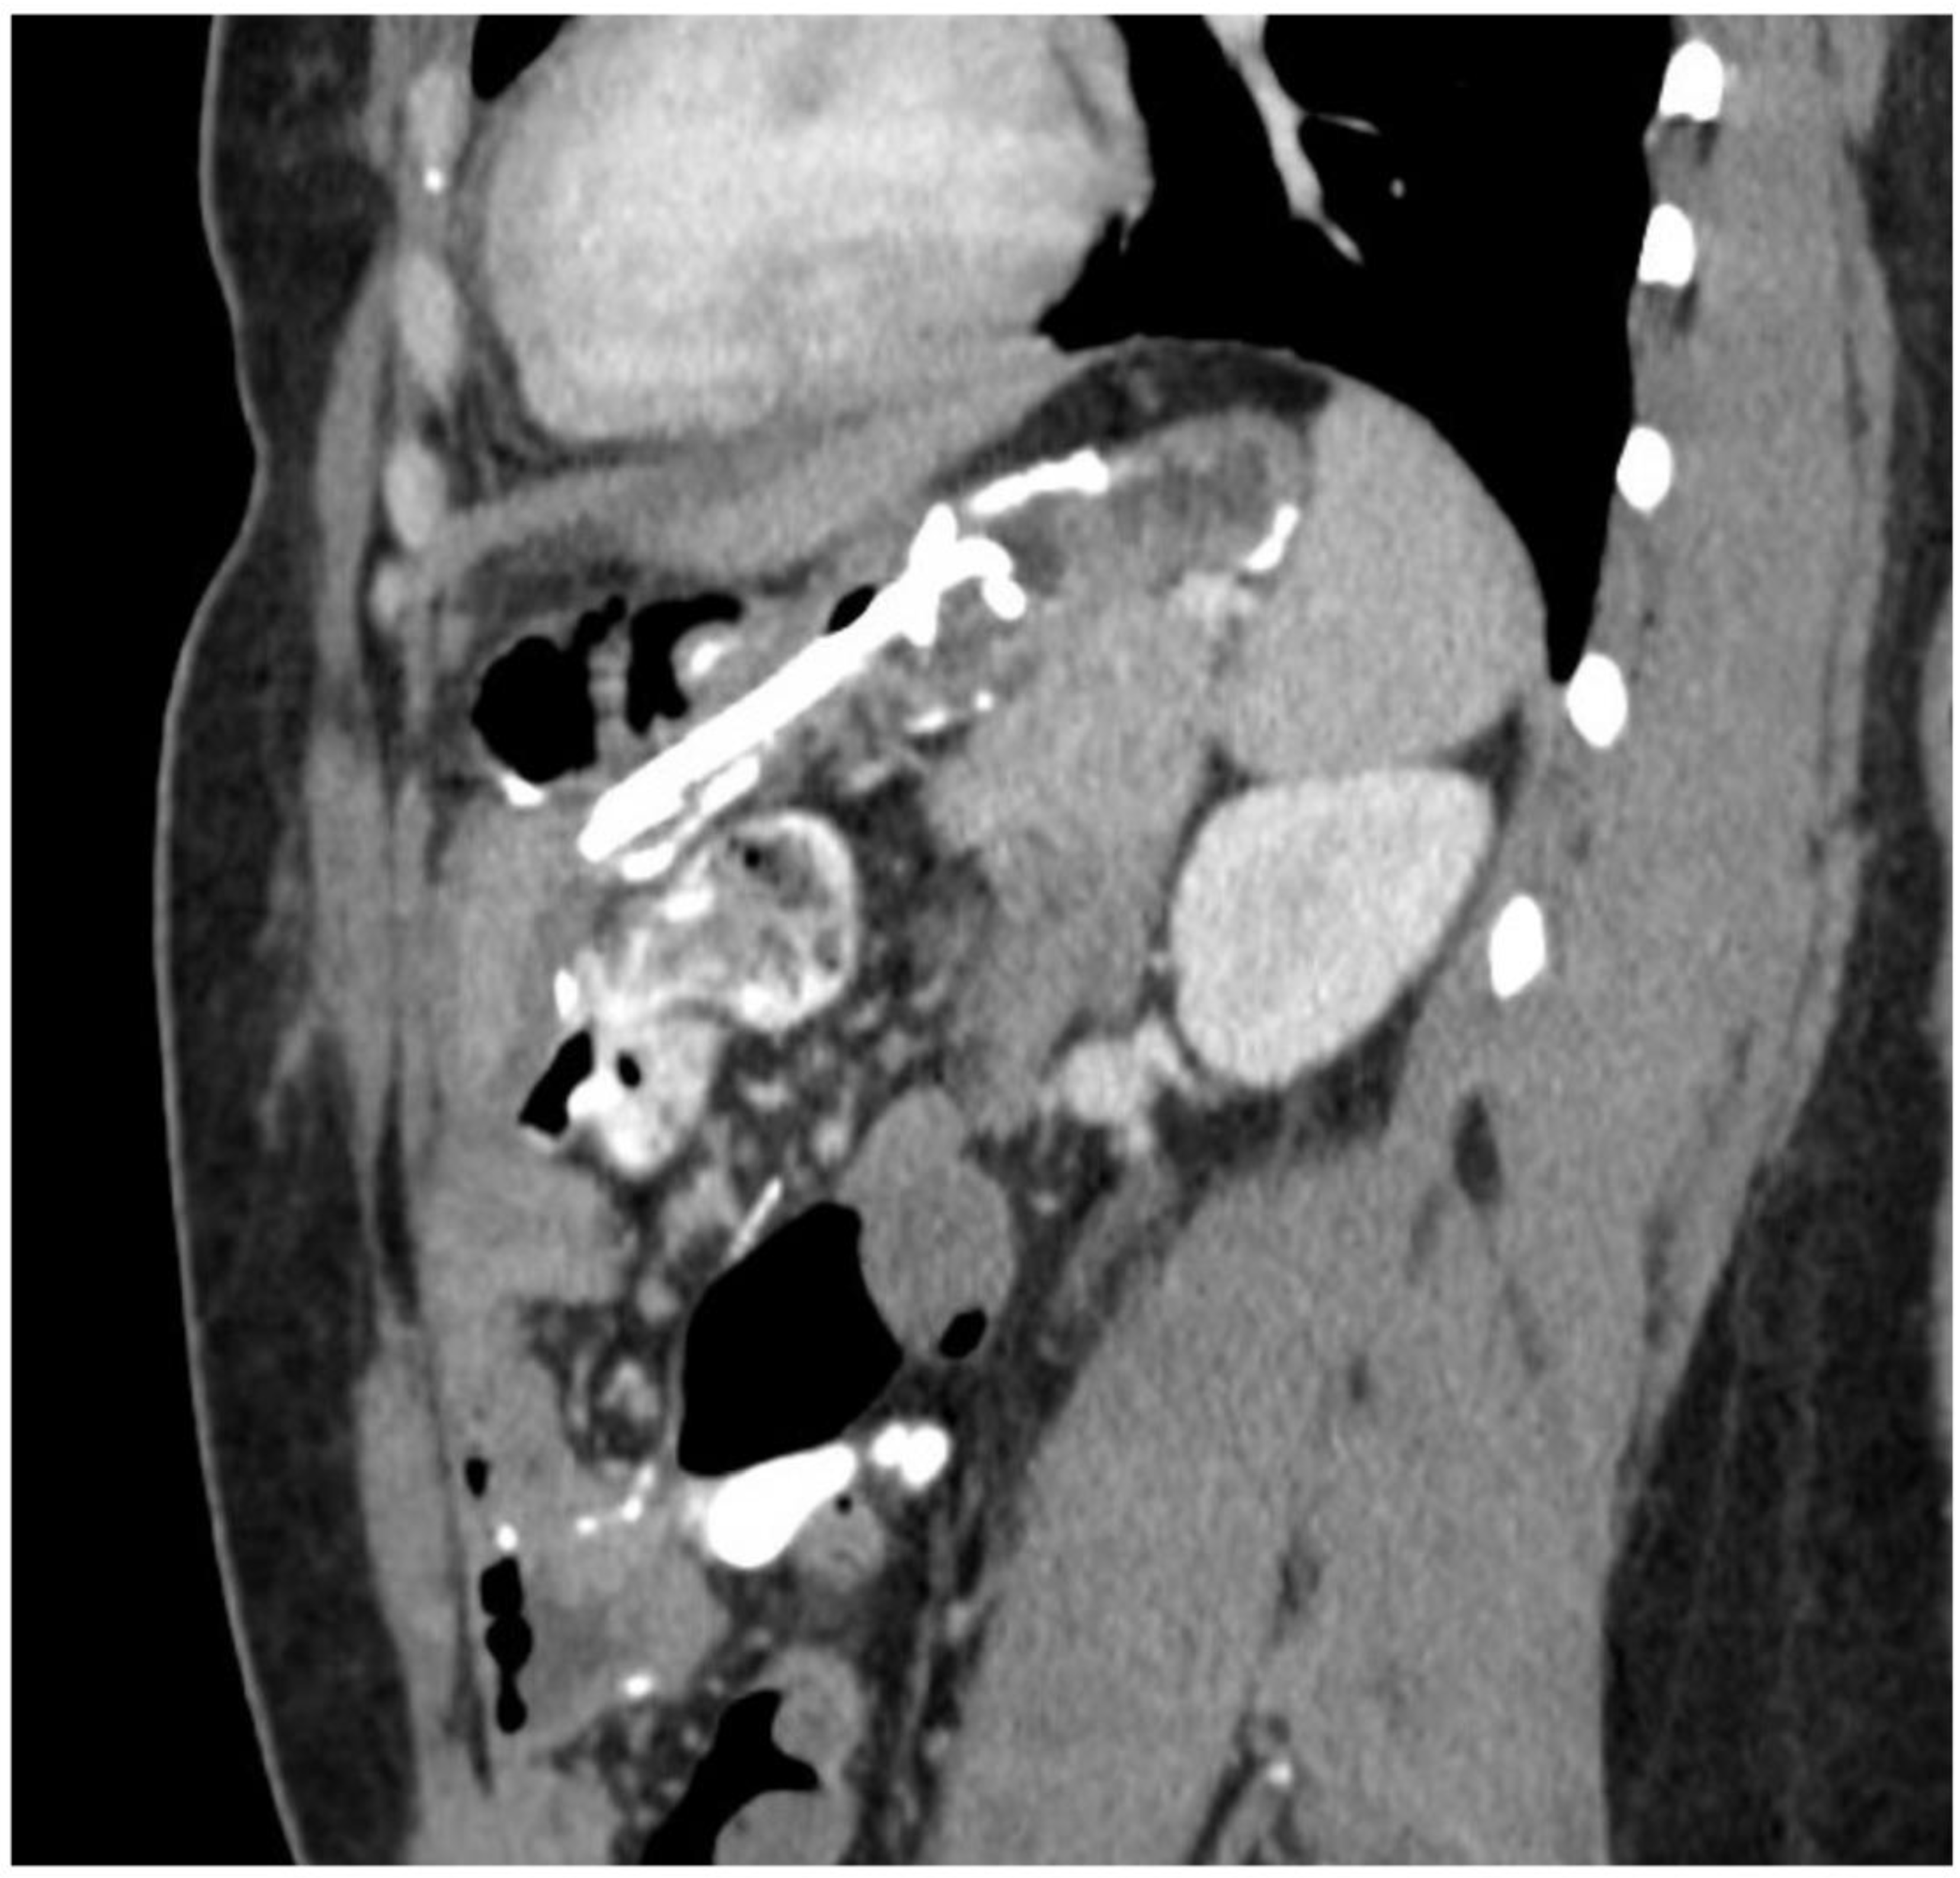

2. Detailed Case Description